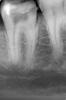

Снежана Опубликовано 25 апреля, 2013 Поделиться Опубликовано 25 апреля, 2013 попались почти подряд 2 шестерки с 5-тью каналами обнаружены без всякого микроскопа. http://img-fotki.yandex.ru/get/6435/32678997.1/0_9f73d_14fafb97_L.jpghttp://img-fotki.yandex.ru/get/5637/32678997.1/0_9f73e_40b93823_L.jpg http://img-fotki.yandex.ru/get/6431/32678997.1/0_9f73c_50036240_L.jpg 9 Ссылка на комментарий

Денис481 Опубликовано 29 апреля, 2013 Поделиться Опубликовано 29 апреля, 2013 посмотрите каналы опять 3 или я пропустил,дистальный белым сразу прошел 0,6 протейпером,он особо и не цеплял,широкий Ссылка на комментарий

Снежана Опубликовано 29 апреля, 2013 Автор Поделиться Опубликовано 29 апреля, 2013 посмотрите каналы опять 3 или я пропустил,дистальный белым сразу прошел 0,6 протейпером,он особо и не цеплял,широкийДенис, на втором снимке выглядит как будто дистальных каналов 2, но может он и 1, просто очень широкий и штифт там болтается.про медиальные по снимкам ничего не могу сказать, нужно смотреть сам зубик. из того, что попадалось мне - если в мезиальной системе обнаруживалось 3 канала, то устья щечного и язычного находились друг от друга достаточно далеко.вы попробуйте заполнить каналы рентгенконтрастом, что-нить вроде метапасты и сделать повторно снимки, лучше повторить проекцию вашего второго снимка, тогда будет яснее в дистальном корне один канал или 2. Ссылка на комментарий